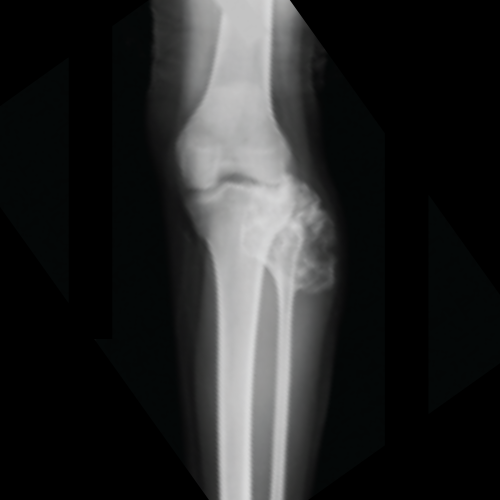

before image of tumours

Before Tumour Surgery